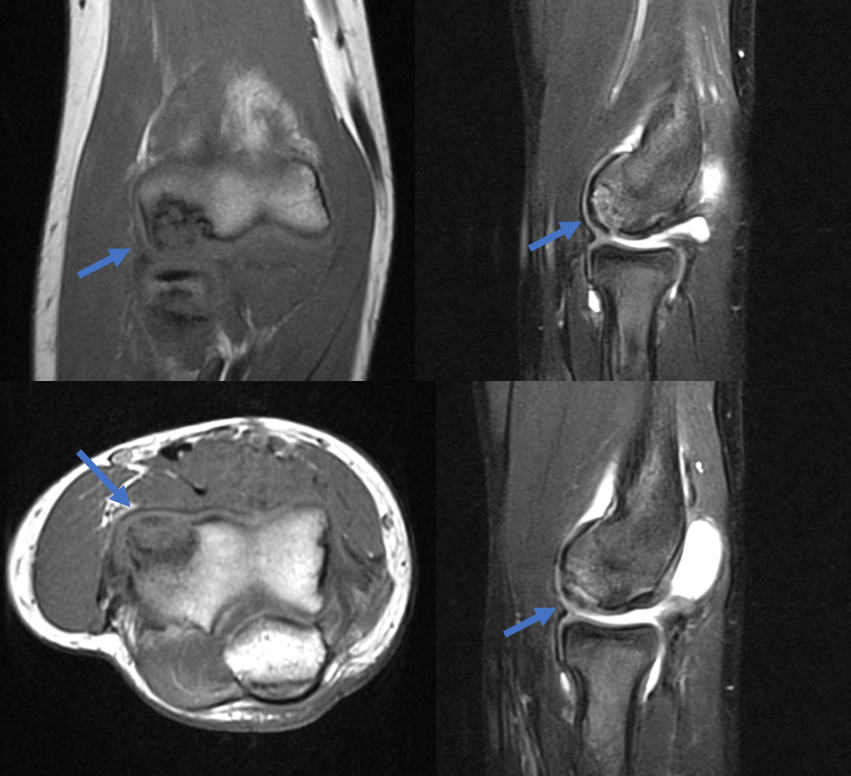

MRI demonstrates an unstable fragmented lesion within the capitellum

- MRI can help define stability of Grade II lesions

- Irregular contour or discontinuity of articular cartilage on MRI suggests unstable lesions